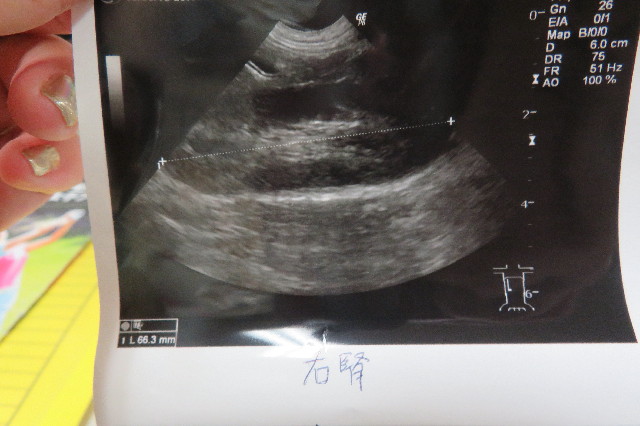

エコーの結果

謎の石がどこからきたものか気になるので、膀胱の炎症の具合と、膀胱に石がないか調べるためのエコーです。

【膀胱の輪切り】

膀胱の内壁が一周、炎症をおこしてかなり晴れています。

内壁が腫れてしまって、おしっこが溜まるスペースが少なくなってしまっているので頻尿になるのでしょうね。

●石はありません(この月齢で石があることは考え難い)